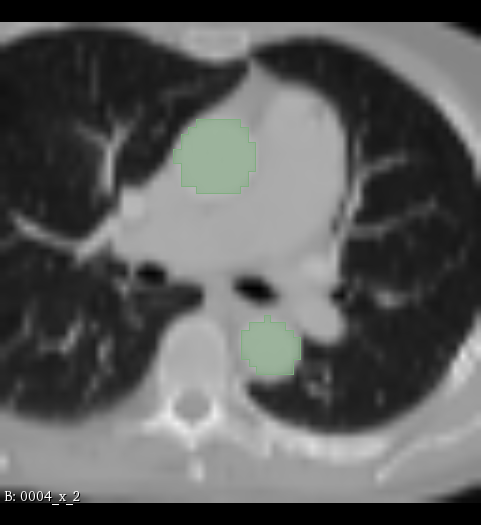

The experiments are conducted with respect to the TotalSegmentor data set [32]. This data set contains 1204 CT images with 104 anatomical structures (27 organs, 59 bones, 10 muscles, 8 vessels). To illustrate the effect noise may have on organs with different shape, three different organs are chosen. This includes the right kidney which in general is pretty spherical, the aorta which is tubular and relatively thick and the esophagus which is tubular and relatively thin. For each of the organs, 400 cases is selected and split into 5 folds of 80 cases. Finally, the images are sub-sample to half resolution and patches of 643superscript64364^{3} voxels centered in each of the structures are extracted.

Table 1: Table over the results from the experiments for each organ and noise level a𝑎a. The entries are average Dice scores obtained from the average over the five folds. CE(0)superscriptCE0\mathrm{CE}^{(0)} indicate that cross-entropy with 1/2121/2 threshold has been used, SD(0)superscriptSD0\mathrm{SD}^{(0)} indicate that soft-Dice with a 1/2121/2-threshold has been used and CE()superscriptCE\mathrm{CE}^{(*)} indicate that cross-entropy with the threshold described in (15) has been used.

Figure 3: Illustration of the results of the experiments presented in Table 1. To the left are the results from the kidney segmentation problem, in the middle are the results from the aorta segmentation problem and to the right are the results from the esophagus segmentation problem. In each of the figures, the average Dice value obtained from five fold experiments is plotted as a function of the noise level a𝑎a. The legend CE(0)superscriptCE0\mathrm{CE}^{(0)} indicate that cross-entropy with the 1/2121/2-threshold has been used, SD(0)superscriptSD0\mathrm{SD}^{(0)} indicate that soft-Dice with the 1/2121/2-threshold has been used and CE()superscriptCE\mathrm{CE}^{(*)} indicate that cross-entropy with the threshold described in  (15) has been used. In all of the reported cases b=0.15/2𝑏0.152b=0.15/\sqrt{2}.

The results from the experiments are shown in Table 1 and Figure 3. This includes the average Dice score obtained for the five different folds and four different noise levels, for each of the different methods of obtaining segmentations: CE(0)superscriptCE0\mathrm{CE}^{(0)}, SD(0)superscriptSD0\mathrm{SD}^{(0)} and CE()superscriptCE\mathrm{CE}^{(*)}.

The first thing to notice is that either all of the the methods perform very similarly, or SD(0)superscriptSD0\mathrm{SD}^{(0)} threshold performs better than CE(0)superscriptCE0\mathrm{CE}^{(0)}. Also, whenever SD(0)superscriptSD0\mathrm{SD}^{(0)} performs better than CE()superscriptCE\mathrm{CE}^{(*)}, cross-entropy with the Dice optimal threshold performs similarly or better than SD(0)superscriptSD0\mathrm{SD}^{(0)}. Simply put, using the alternative threshold (15) with cross-entropy yields the performance of soft-Dice. The second thing to notice is that the difference amongst the methods increases when noise increases. That is, for small noise, the performance of the methods are almost equivalent, but as the noise increases, the associated scores start to diverge. This type of result is expected from the theory and depicted in Figure 1.